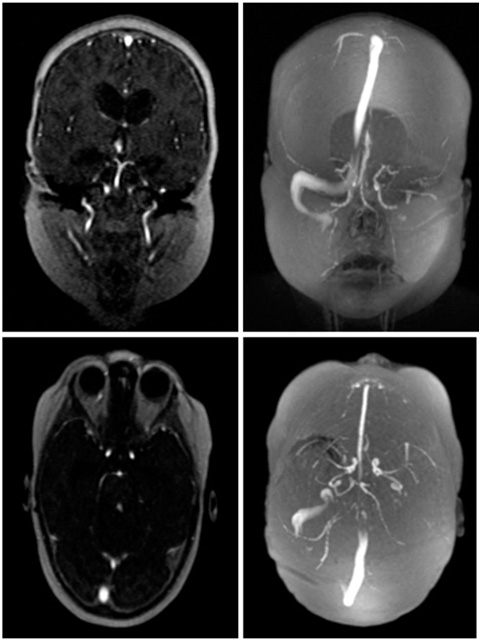

3D CE-MRV:

- Power inject contrast

- 3 acquisitions: Pre-contrast mask, 1 min post-injection, 3 min post-injection

- Create subtraction spinner 3D MIPs using mask and 1 min acquisition

| SAG | T1 | 3D CE-MRV | ~1 mm | ~ 0 mm | No | 24cm | See note above |